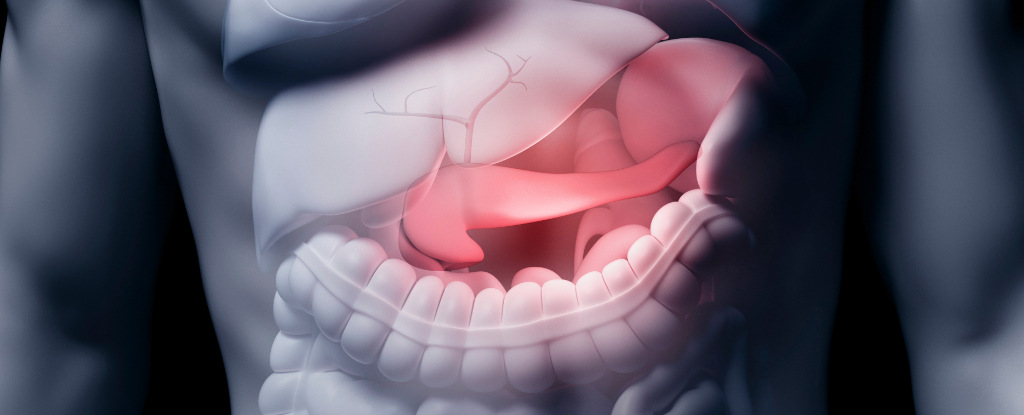

Insulin Is Produced in More Areas Than Just the Pancreas. Discover Another Unexpected Place.

Understanding Insulin Production in the Brain Interestingly, your brain is capable of producing insulin, which is the same type that your pancreas produces. This is particularly relevant for those with type 1 diabetes, who lack insulin production, and for individuals with type 2 diabetes, where insulin doesn’t function correctly. For over a century, scientists have […]